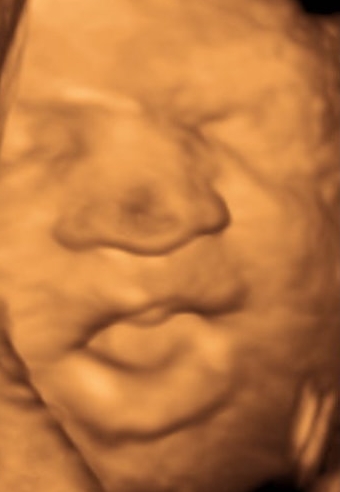

18 week Gender Scan, UPDATE!! from previous post 12 week 4 days scan :)